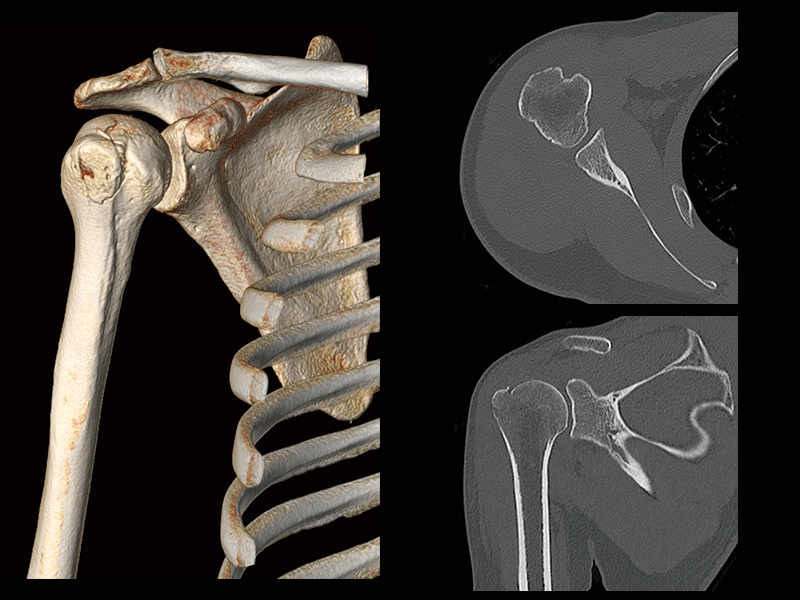

Humeral greater tuberosity fracture

- * Images other than the axial image were processed by the 3D image analysis system SYNAPSE 3D.